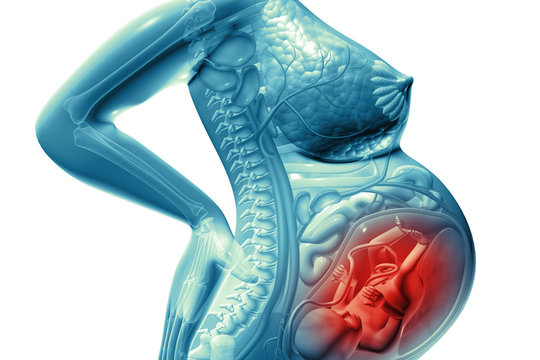

Физиология беременности: строение органов

Раздел: Моменты озарения